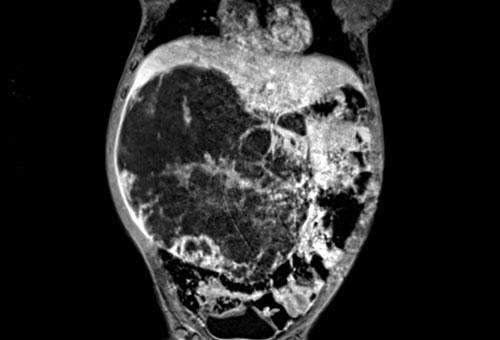

Hình ảnh MRI của một bé gái chín tháng tuổi có khối u ở bụng trái. MRI cho thấy khối u tuyến thượng thận trái, một phần đặc, một phần nang. Có nhiều di căn gan.

Khối u đã được sinh thiết. Có tình trạng chảy máu liên tục qua kim dẫn đường. Vào cuối thủ thuật, hai nút bọt gelatin đã được đặt vào (các dải tăng âm (mũi tên)).